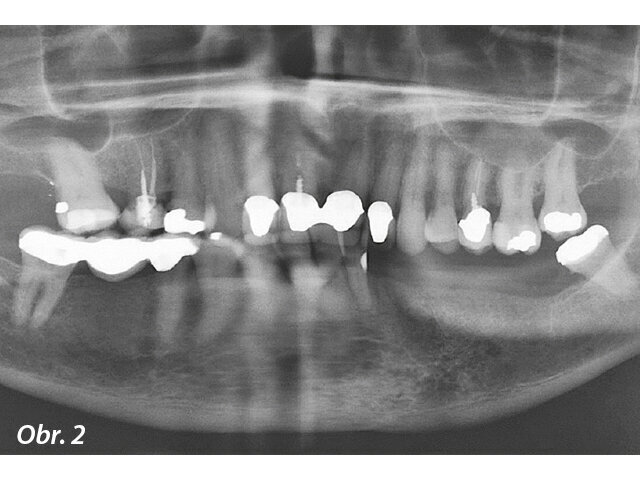

Následovalo plánování založené na počítačové tomografii (CBCT), zbývající mandibulární zuby pacientky byly extrahovány. Bylo provedeno plánování léčby implantáty v softwaru SimPlant (Dentsply Sirona Implants), který ukázal vhodnou polohu zubů a odhadovanou polohu frontálních implantátů (OsseoSpeed EV) a distálních implantátů (OsseoSpeed Profile EV) v mezích navrhované finální náhrady (obr. 3).

Obr. 3: Plánování implantace prováděné pomocí softwaru SimPlant (Dentsply Sirona Implants)